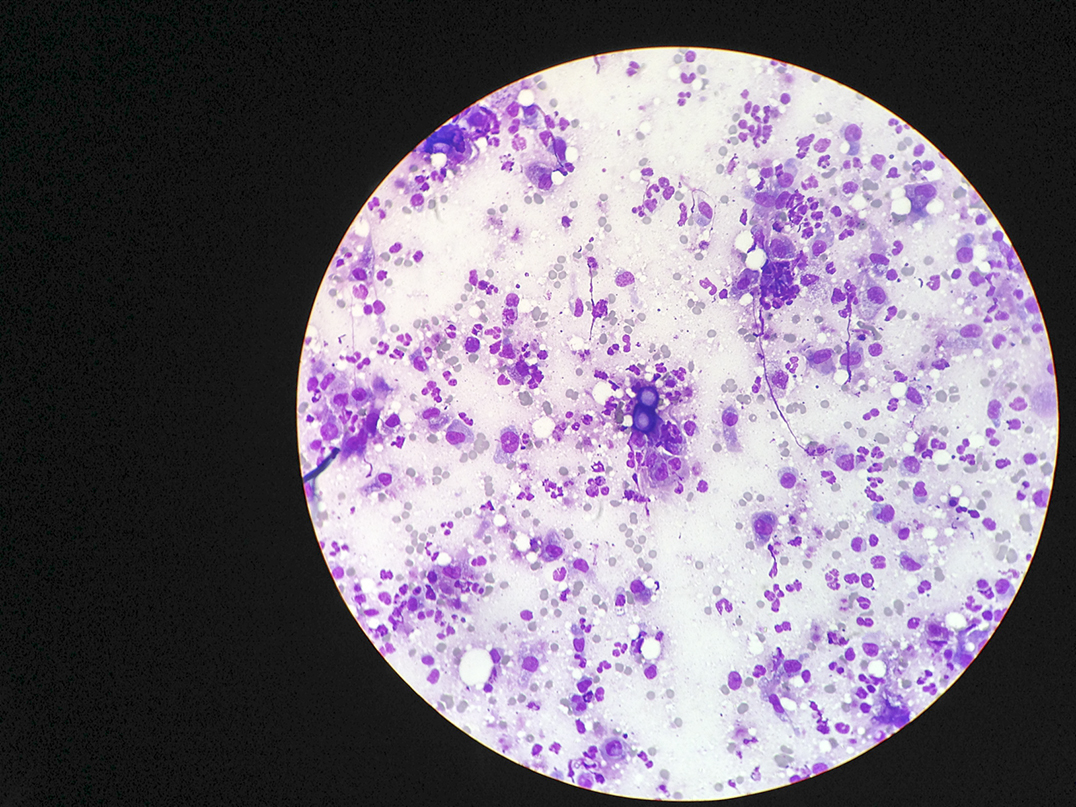

By way of a recap, blastomycosis is a fungal spore found in rotted wood, vegetation and soil with low pH levels that, when breathed in (it can also be contracted through a cut in the skin, but this is more rare), can cause the spore to germinate within the body (typically the lungs) which can also spread to the central nervous system. It is often mistreated as pneumonia or even lung cancer as chest x-rays will show lesions on the lungs and patients will often present with a lingering cough, shortness of breath and, sometimes, weight loss.

At this same time our cat Rudy, a big strapping fellow with a love of food, was becoming ill. He had already been treated for a wound on his front leg that required minor surgery and antibiotics, but it wasn’t getting better. Back for another trip to see his vet, Dr. Paquet, and the concern of blasto was mentioned. A chest x-ray showed spots on his lungs and a sample from a lesion found on his head also confirmed the news—the little purple figure eights of yeast showed Rudy had blasto, likely because of the backyard construction. He was immediately placed on itraconazole and given a 30 to 50 percent chance of survival. This was two weeks ago.